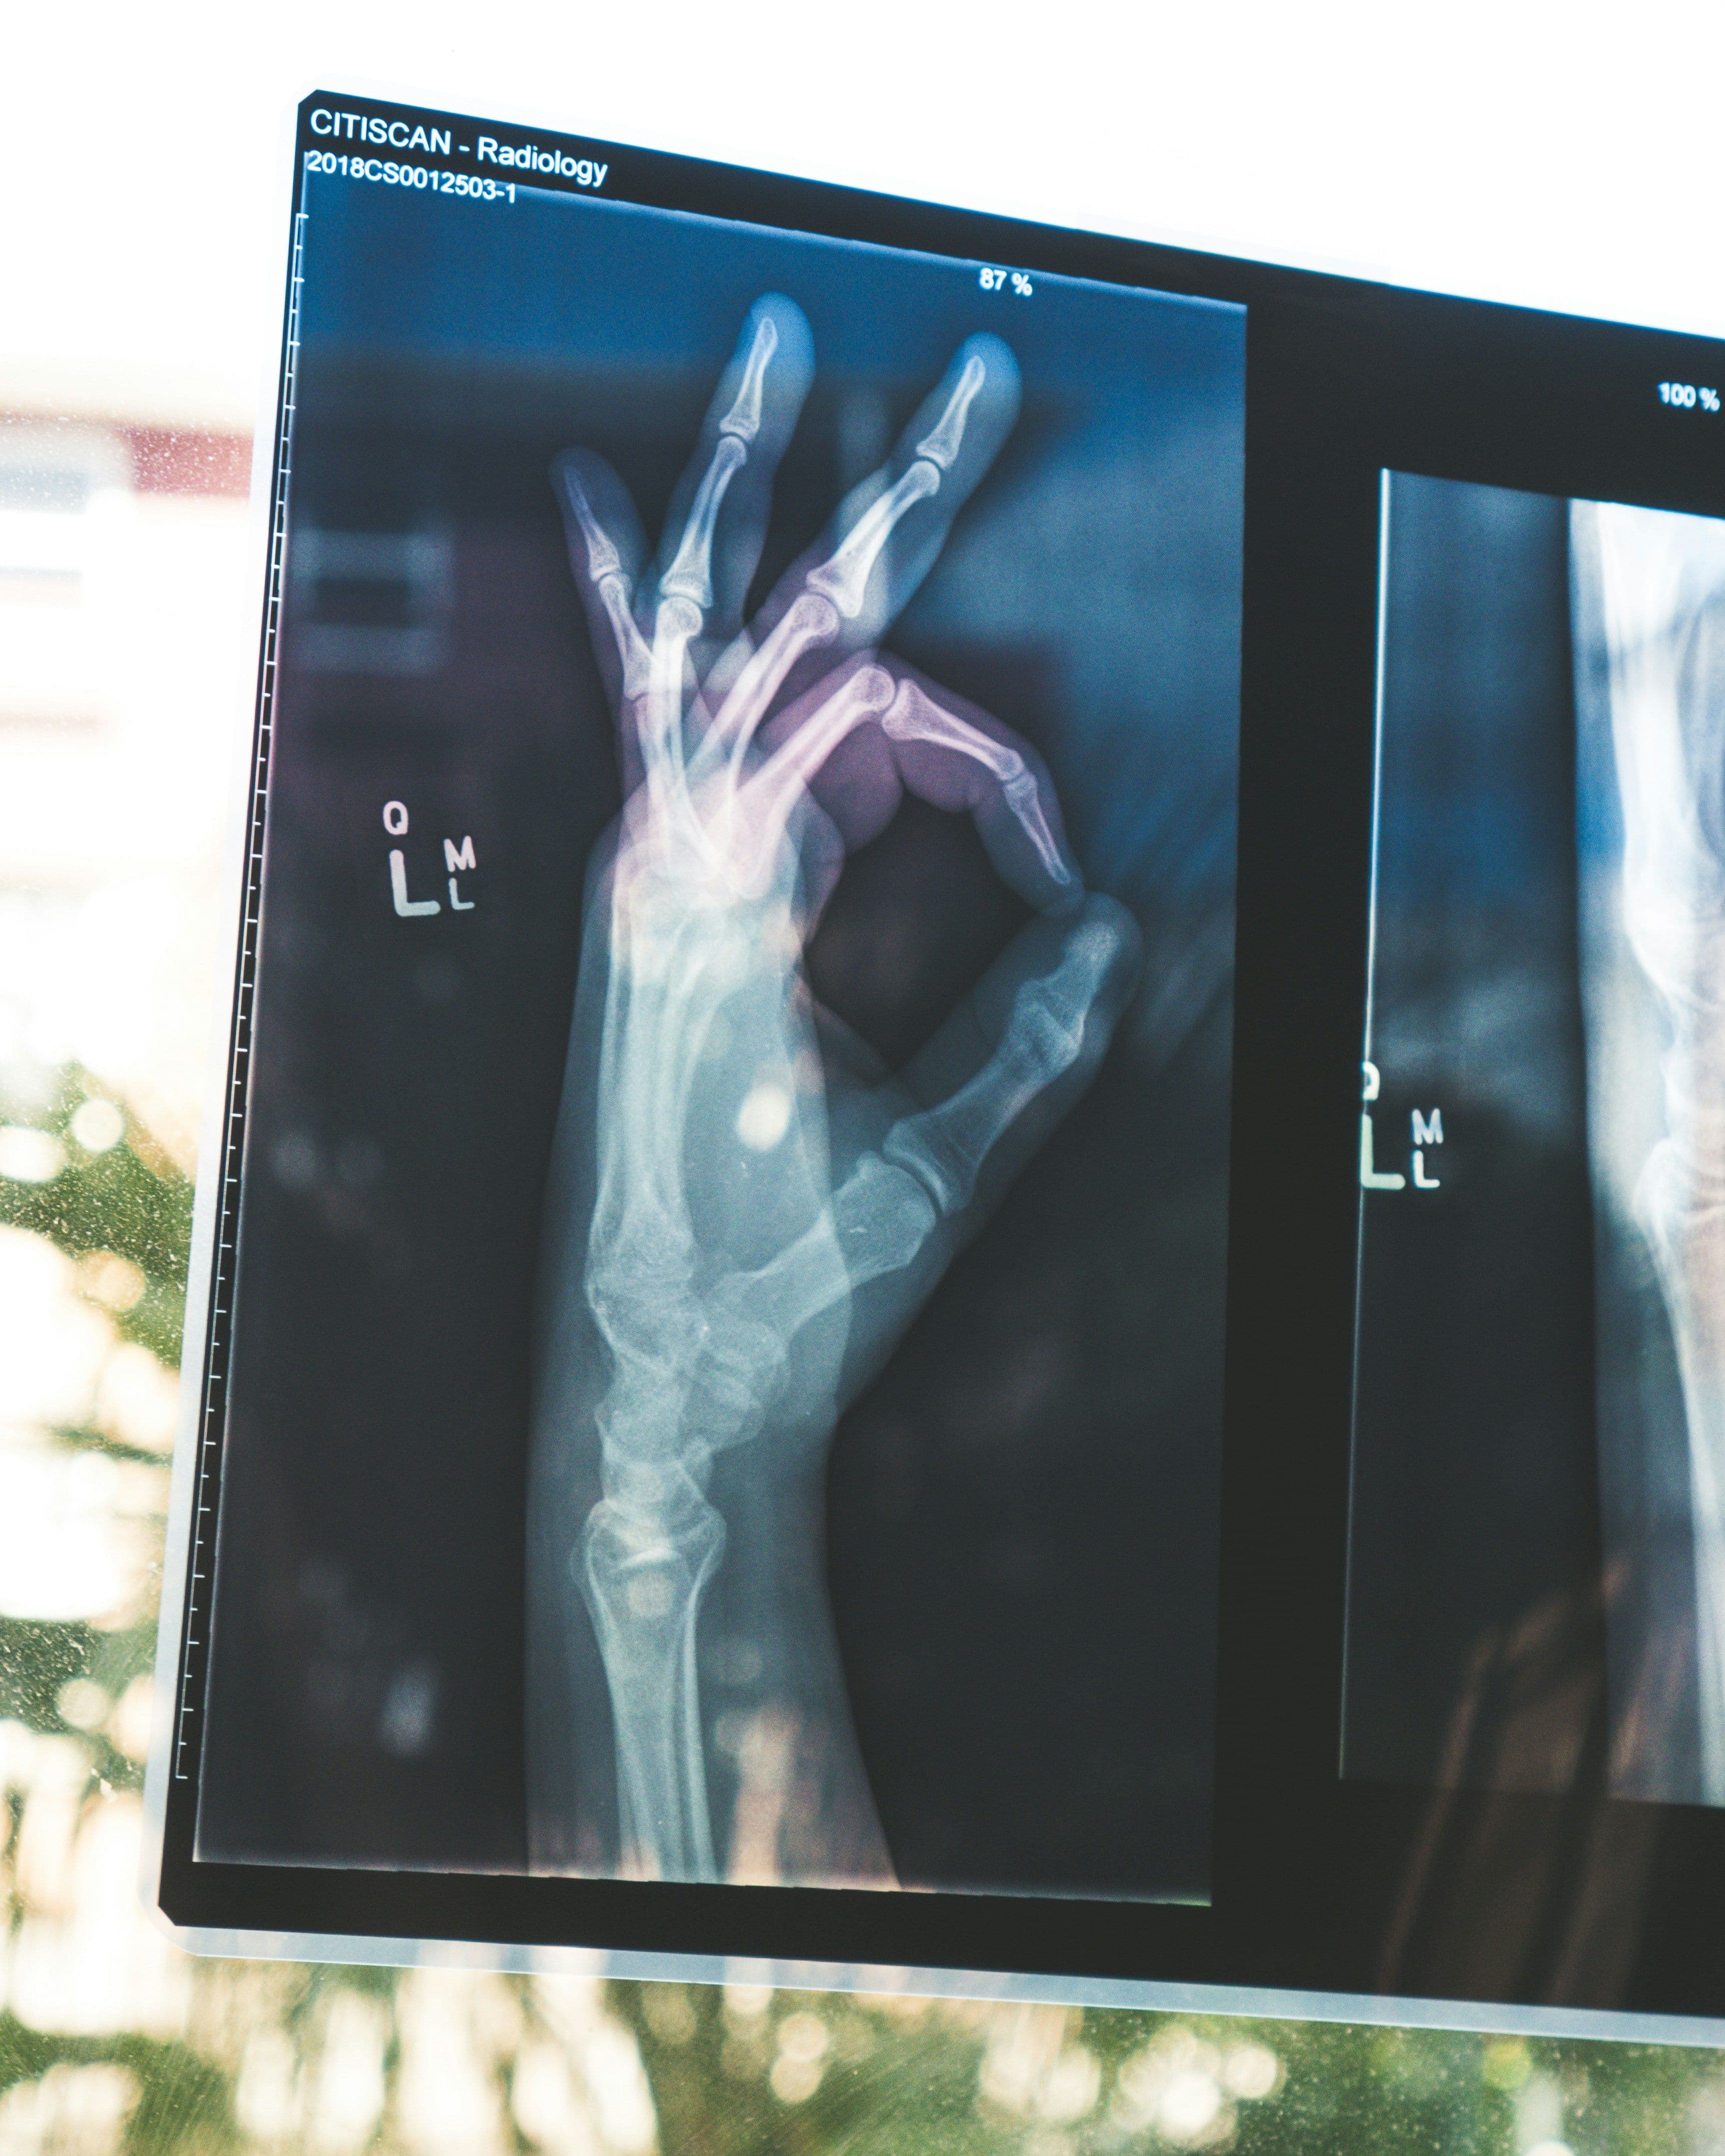

What comes to mind when you hear "medical technology?" Some amazing innovations have completely changed how we prevent, diagnose and treat diseases over the last century. From the X-ray that lets doctors see our bones to artificial joints that restore mobility, modern medicine would be unrecognizable without tech.

X-rays were actually discovered accidentally in 1895 by Wilhelm Röntgen playing with a cathode ray tube. By noticing a fluorescent glow, he realized a new type of ray was being emitted that could produce images of the inside of the human body without surgery! This simple discovery paved the way for today's digital radiography systems.

When something does go wrong with our health, the first step is pinpointing the problem through medical testing and diagnostic tools. We're probably all familiar with techniques like X-rays, CT scans, MRIs that use radiation or magnets to capture images of what's happening inside our bodies.